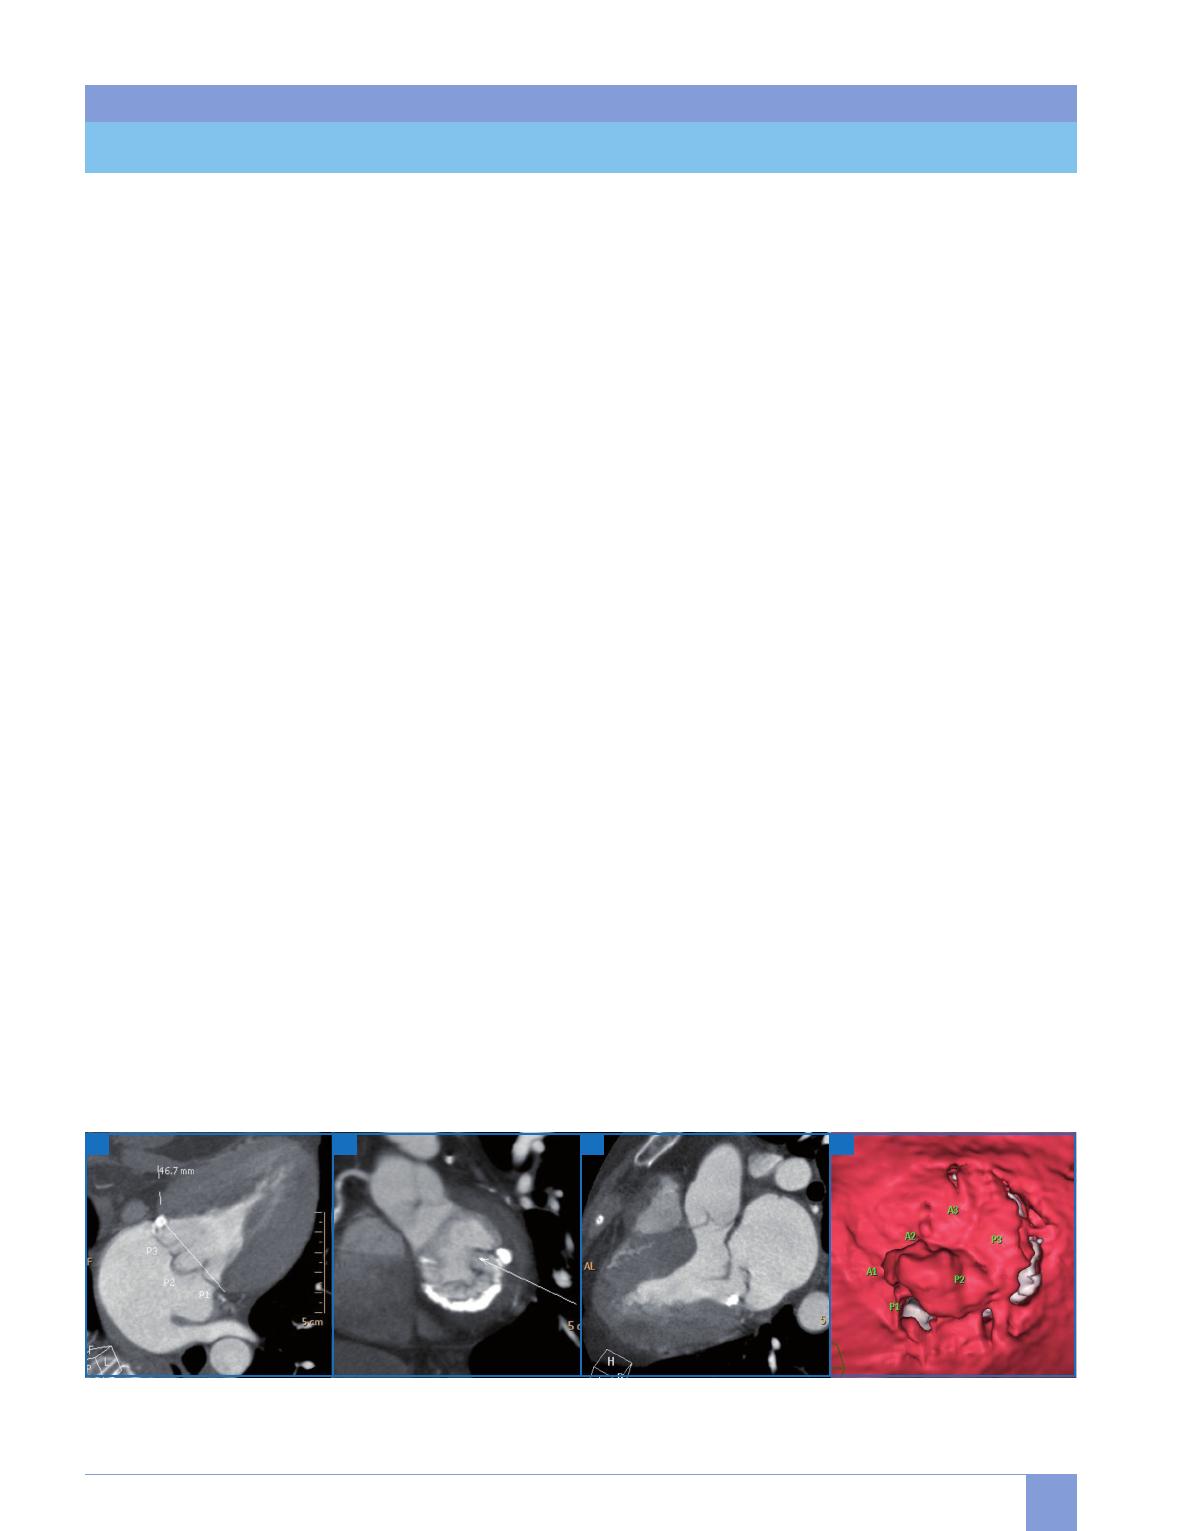

A B C D

Fig. 7 : Insuffisance mitrale. Prolapsus de la valve postérieure prédominant sur P2, en coupes (A, B, C) et 3D volumique depuis l’intérieur de l’oreillette gauche

(D), avec la segmentation mitrale.

[ Insuffisance mitrale (fig. 7)

De par ses propriétés physiques, le scan-

ner se prête particulièrement à l’étude

géométrique de la valve mitrale [9], et

peut surtout être utile dans l’analyse du

mécanisme (prolapsus, dilatation, res-

triction) avec segmentation des feuillets

et de l’étiologie (fonctionnelle, dystro-

phique, rhumatismale, ischémique).

En raison d’une résolution temporelle

inférieure à l’échographie, un cordage

rompu et hypermobile reste difficile-

ment visible, contrairement à l’appareil

sous-valvulaire en position anatomique

normale. De même, les feuillets relati-

vement fins et très mobiles de la valve

mitrale fuyante sont plus difficiles à

visualiser en scanner que les feuillets

aortiques, rendant la planimétrie de

l’orifice régurgitant inconstamment

réalisable, mais alors correctement cor-

rélée à la quantification échographique.

Comme pour l’IA, l’équation de conti-

nuité entre les ventricules droit et gauche

permet d’estimer la fraction régurgitée

en l’absence de valvulopathie associée.